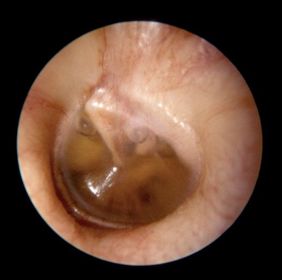

OTITIS SEROSA MEDIA